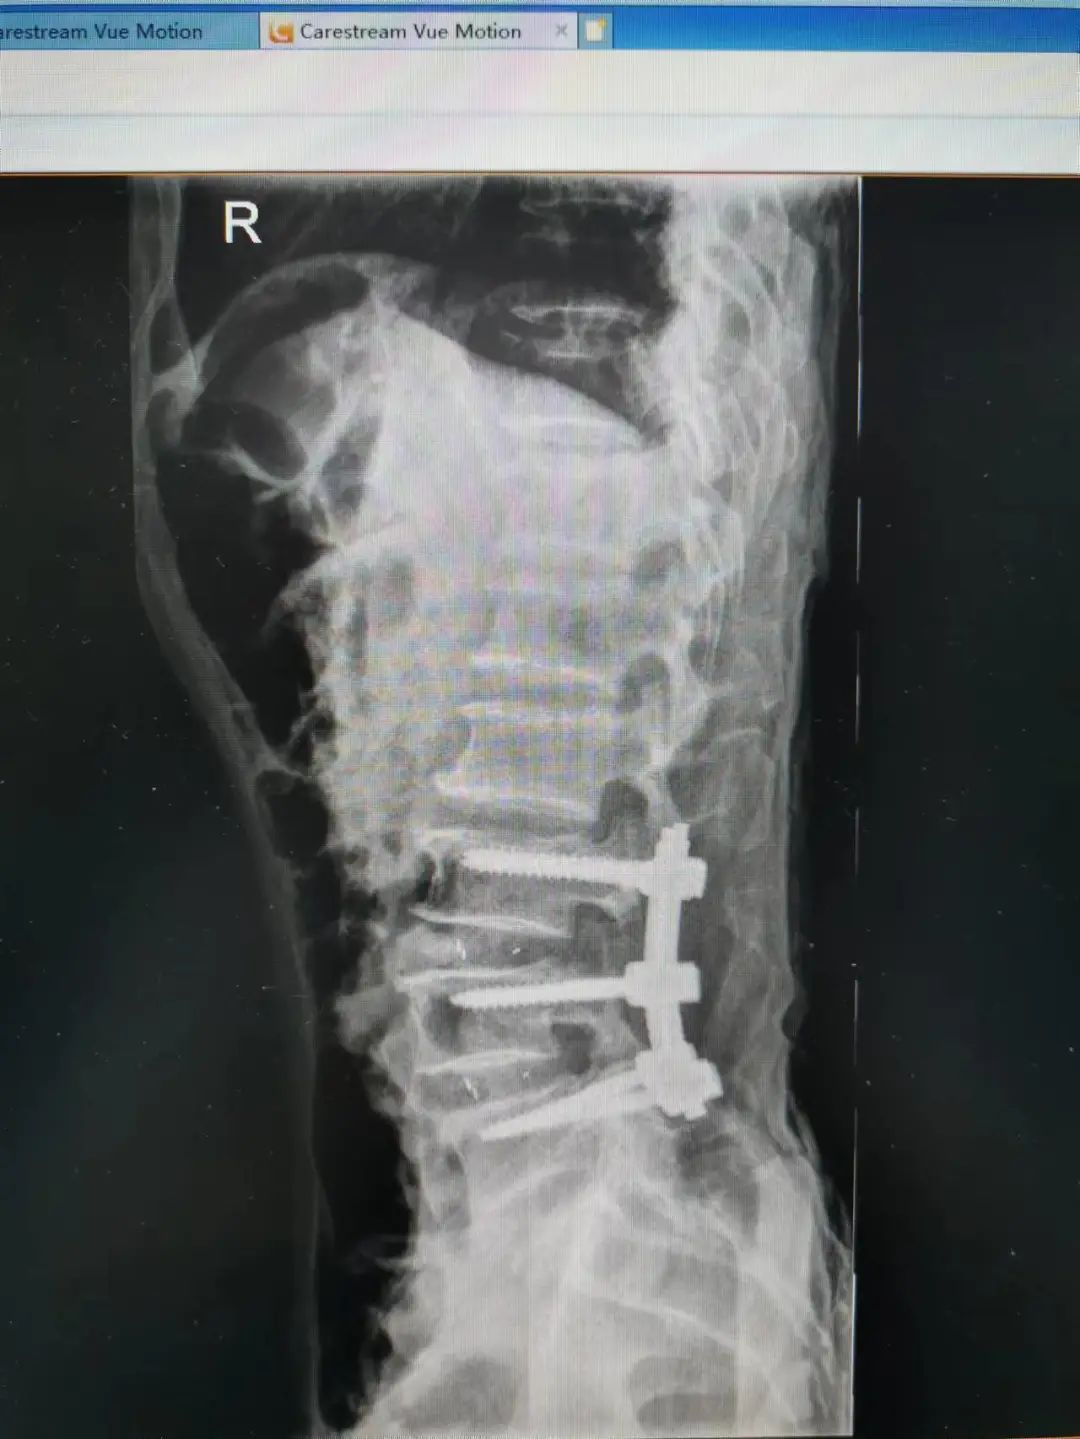

杨先生术后拍片

由于杨先生的病情严重,需住院治疗。杨先生入院后,泸州市中医医院骨伤二科科主任杨陈一制定了手术计划,决定脊髓型颈椎病的手术从前路切开减压,颈3/4 、颈4/5、 颈5/6、 颈6/7椎间盘切除,椎间融合,钢板内固定术手术,而腰椎管狭窄症经后路切开减压,腰3/4、腰4/5椎同盘动除,椎间融合、钉棒系统内固定术。